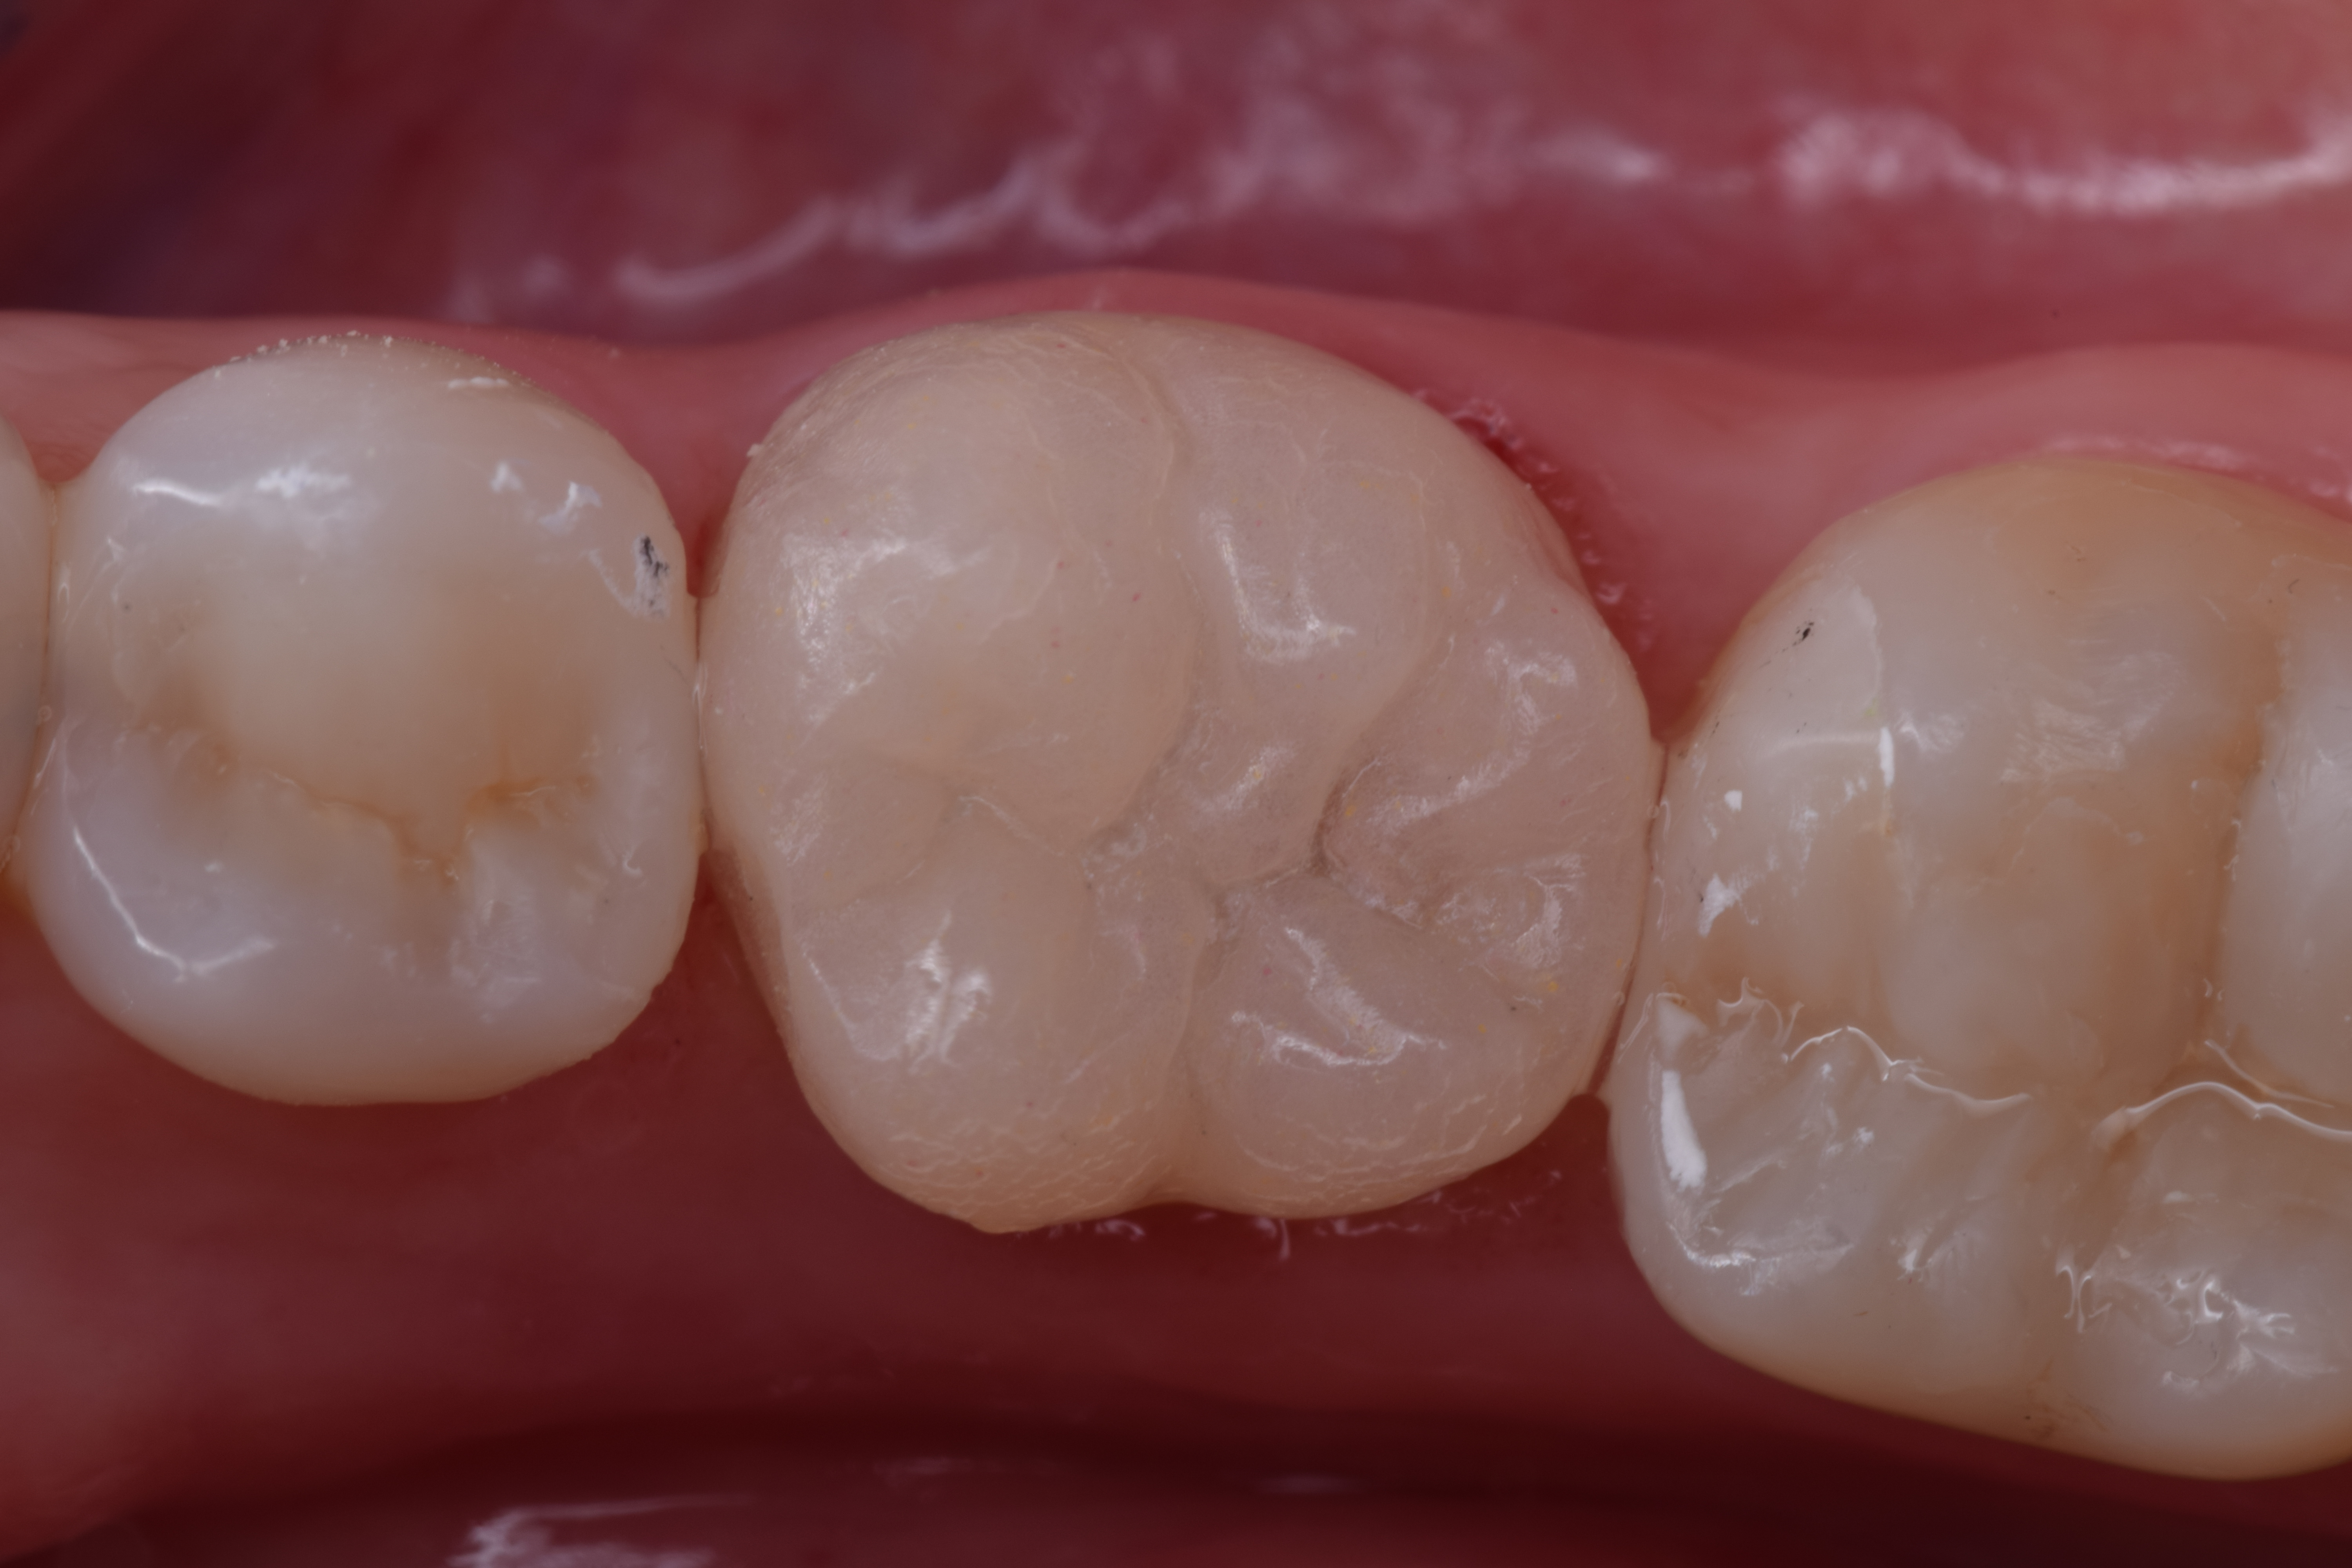

The purpose of this clinical case description article was to present the planning sequence, indication, treatment and performance to obtain a crown of the Endocrown type. This clinical case description article illustrates a therapeutic option for functional and esthetic rehabilitation of a devitalized mandibular molar, presenting a small amount of remaining coronal tooth structure, by means of cementing a pure porcelain crown of the Endocrown type (Adhesive Endodontic Crown). A 39-year-old woman presented to the Graduate clinic of the Bauru Dental School (FOB), University of São Paulo (USP), with the complaint that tooth #36 had an extensive and unsatisfactory composite resin restoration. The lithium disilicate-based system of monolithic porcelain was used with the lost wax technique. This therapy promoted the stability and retention of the indirect restoration, without the need for performing reconstruction of the above mentioned tooth, either by means of a cast metal core or reconstruction with intracanal post, thereby reducing the treatment time. After the tooth preparation, the provisional restoration was done with acrylic resin to determine if the retention and stability of the remaining tooth was adequate to receive the indirect Endocrown restoration. The characteristics of the internal and external walls of the dental remnants, cervical termination, impression-taking, laboratory stages and adhesive cementation will be discussed. The major advantage of indicating an endocrown is the use of the dental remnants itself, particularly the pulp chamber, to promote retention and stability in cases without adequate height for performing complete dental and crown reconstruction.